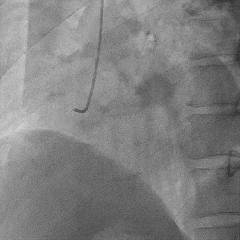

术后冠脉造影:

术后即刻冠脉功能学全面评估:

▶IMR:18;CFR:3.2;FFR:0.89。